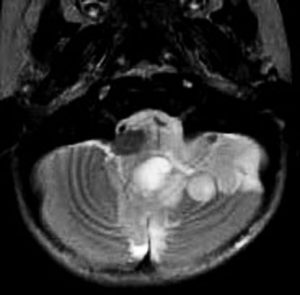

第4脳室床に発生した典型的な上衣腫 EPN-PFA の画像です。水頭症になって,頭痛と嘔吐,意識障害で発症しました。典型的なMRI画像と病理所見です。MRIでは第4脳室からマジャンディー孔を越えて脊髄背側まで長く腫瘍が伸びています。腫瘍内部に小さなのう胞が複数みられます。病理像では,血管周囲に細胞核がない無核野が認められます。血管周囲に伸びた繊細な単極性突起が集まった領域です。これは,血管周囲偽ロゼット perivascular pseudorosette という上衣腫に特徴的な病理所見です。

幼児の巨大な上衣腫です。左ルシュカ孔から延髄を取り囲む様に小脳延髄角槽に進展しています。最も典型的で治療が難しいタイプです。これはT2強調画像ですが,ガドリニウム増強されないものでした。

左が術前,右が術後です。脳底動脈の周囲が摘出できませんでした。幼児ですが手術後には局所照射をするしか方法がありません。